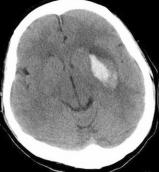

323页7题图片 |

原图 |

替换为此图